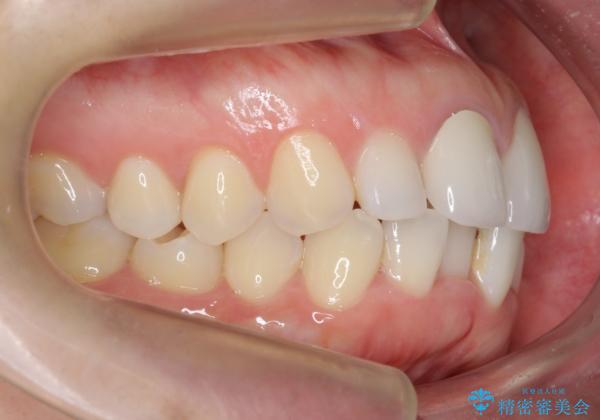

開始前

-